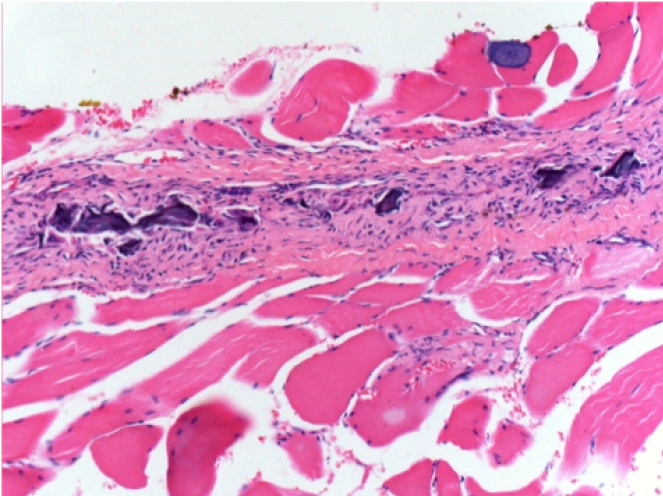

1 mes después de la inyección de Endopeel 0,1 ml en el músculo pretibial derecho.

¡Lo que se ve en negro en las imágenes no es una necrosis como podrían imaginar algunos científicos!

De hecho, hay que tener en cuenta 4 conclusiones